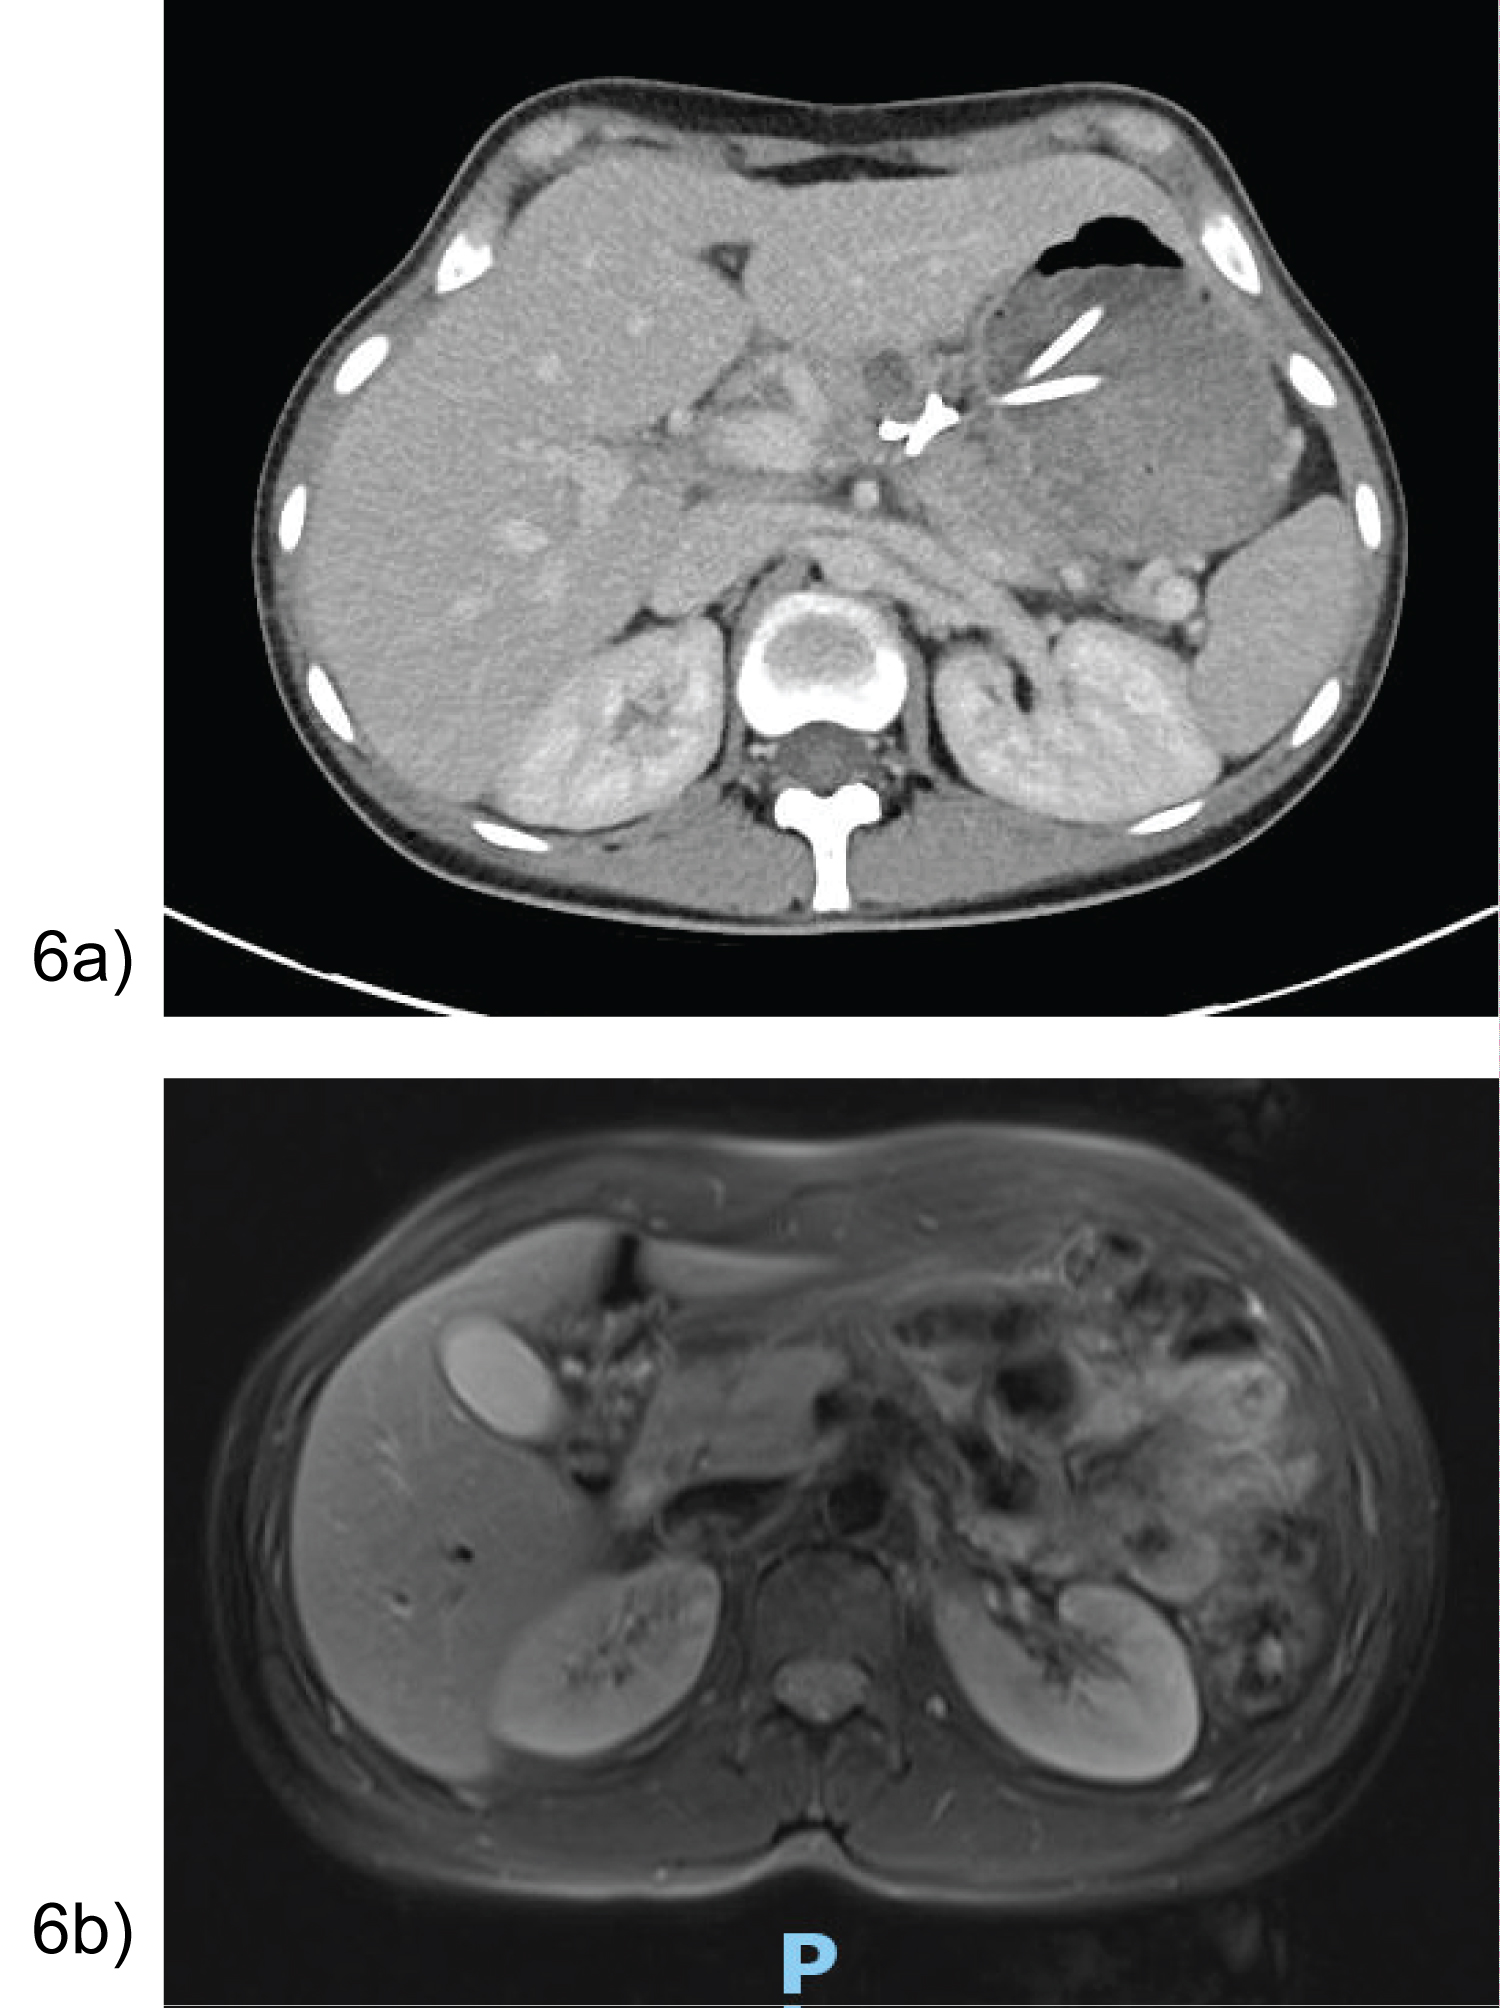

Majority of patients were asymptomatic with no signs of pancreatic endocrine or exocrine insufficiency over the course of a 10-36 month follow-up. All patients had significant improvement in pseudocyst size as demonstrated in Figure 6a. Case 1’s MRI at 36 months depicted a normal head and uncinate process, with distal atrophy of the pancreas and MPD (Figure 6b).

Figure 6: (a) Case 7- CT day 15 post cystogastrostomy showing stents in position with interval decrease in peripancreatic collection; (b) Case 1- MRI 36 months post EUS cystogastrostomy with distal pancreatic atrophy and duct. View Figure 6